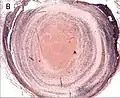

| A recent pulmonary thrombo-embolus with prominent lines of Zahn. The pale areas consist of fibrin and platelets. The red areas consist of erythrocytes. | |

Thrombus showing circumferential lines of Zahn.